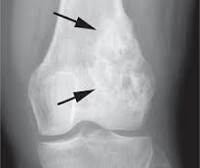

В начальной стадии на рентгенограммах определяется остеопороз и смазанность контуров опухоли. В последующем выявляется дефект костной ткани. Нередко наблюдается характерная картина отслоения надкостницы с образованием «козырька». У детей часто обнаруживается игольчатый периостит - тонкие костные образования (спикулы), расположенные перпендикулярно по отношению к кости. На рентгеновском снимке такие образования создают типичную картину «солнечных лучей».